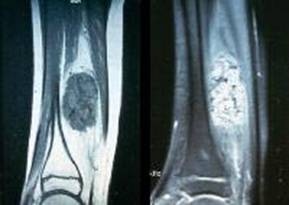

Gambar 3. Hasil pencitraan T1 dan T2 MRI dari intramuscular hemangioma pada kaki. Gambaran yang menyerupai ular pada pembuluh darah menunjukkan tanda yang kuat dari hemangioma (Katz, et al., 2002).

Gambar 4. T1 (time to repetition [TR]=500, time to echo [TE]=15.0/1) dan T2 (TR=3000, TE=15/Ef) hasil pencitraan pada intramuscular hemangioma pada kaki. Hemangioma radiolusen pada T1 dan radioopak pada T2 menunjukkan bahwa hemangioma seperti gambaran lemak atau hasil nonliquid (Katz, et al., 2002).